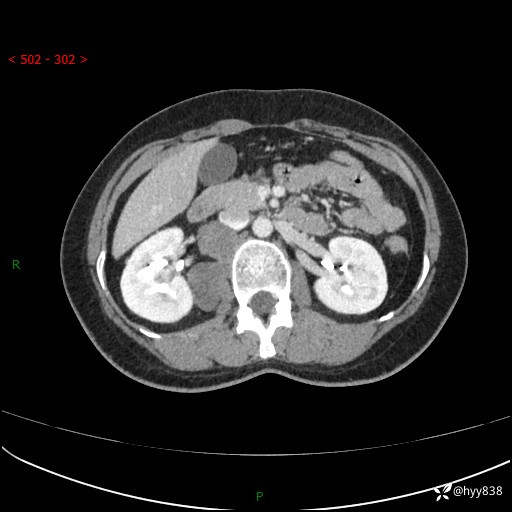

简要病史:患者于1天前因体检发现右旁肾占位,无肉眼血尿,无畏寒发热,无咳嗽咳痰,无腰腹部疼痛不适,无尿频尿急症状,起病来,患者未行特殊治疗,为求进一步诊治,门诊以"右侧腹膜后肿物"收治入院。 发病来患者精神、饮食、睡眠良好,小便如上,大便正常,体重无明显变化。

辅助检查:CT

临床诊断:腹膜后肿物

上腹部CT增强(动脉期+实质期)(外院平扫)